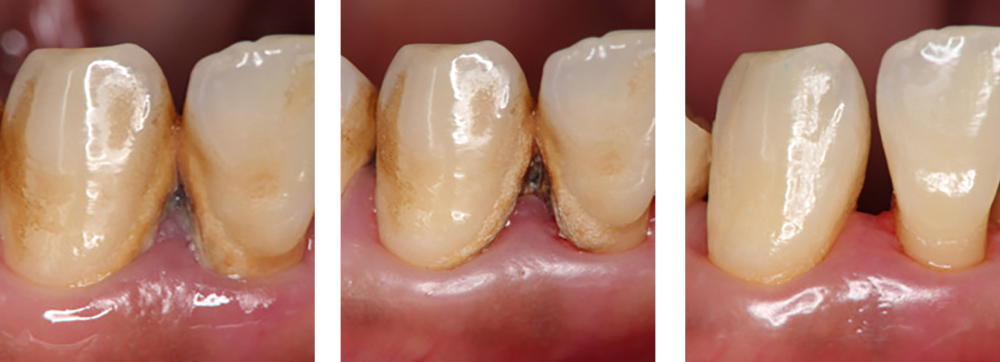

歯周病治療

術前

術中

術後

| 治療内容 | 歯磨き指導を行い、歯肉の発赤・腫脹が改善されたため歯石除去を行った |

|---|---|

| 治療期間・回数 | 1カ月・3回 |

| 費用 | 保険適用となります |

| リスク・副作用 |

|